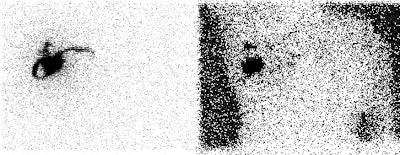

Internal mammary node drainage: The patient underwent lymphoscintigraphy as part of a sentinel node dissection procedure. An intradermal injection was performed in the right breast at the 2 o'clock position over the patients breast cancer. An anterior and transmission image are shown below. Drainage to both the right axillary and right internal mammary nodes (black arrow) can be seen. Although the internal mammary nodes were not dissected at surgery, it is important to note this activity if post operative adjuvant radiation therapy is planned. |